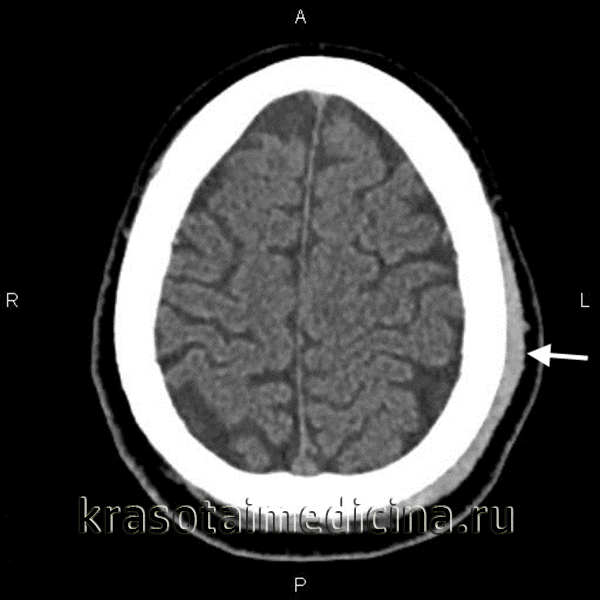

Компьютерная томография головного мозга. Гематома периферических мягких тканей левой теменной области.